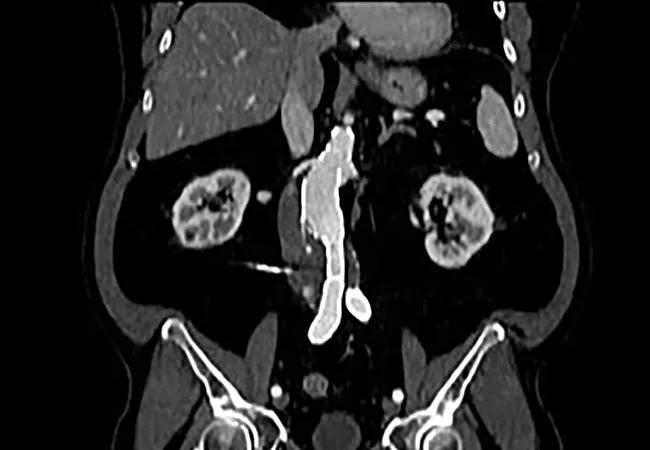

imaging study showing abdominal aortic aneurysm

Conventional open surgery is still an important strategy for patients needing elective repair of an abdominal aortic aneurysm (AAA), despite widespread use of less-invasive endovascular aneurysm repair (EVAR) options. Many patients present with anatomic features — most commonly a short aortic neck or a tortuous iliac artery — that preclude the use of a fenestrated endovascular aneurysm repair (FEVAR) device according to the device’s instructions for use.